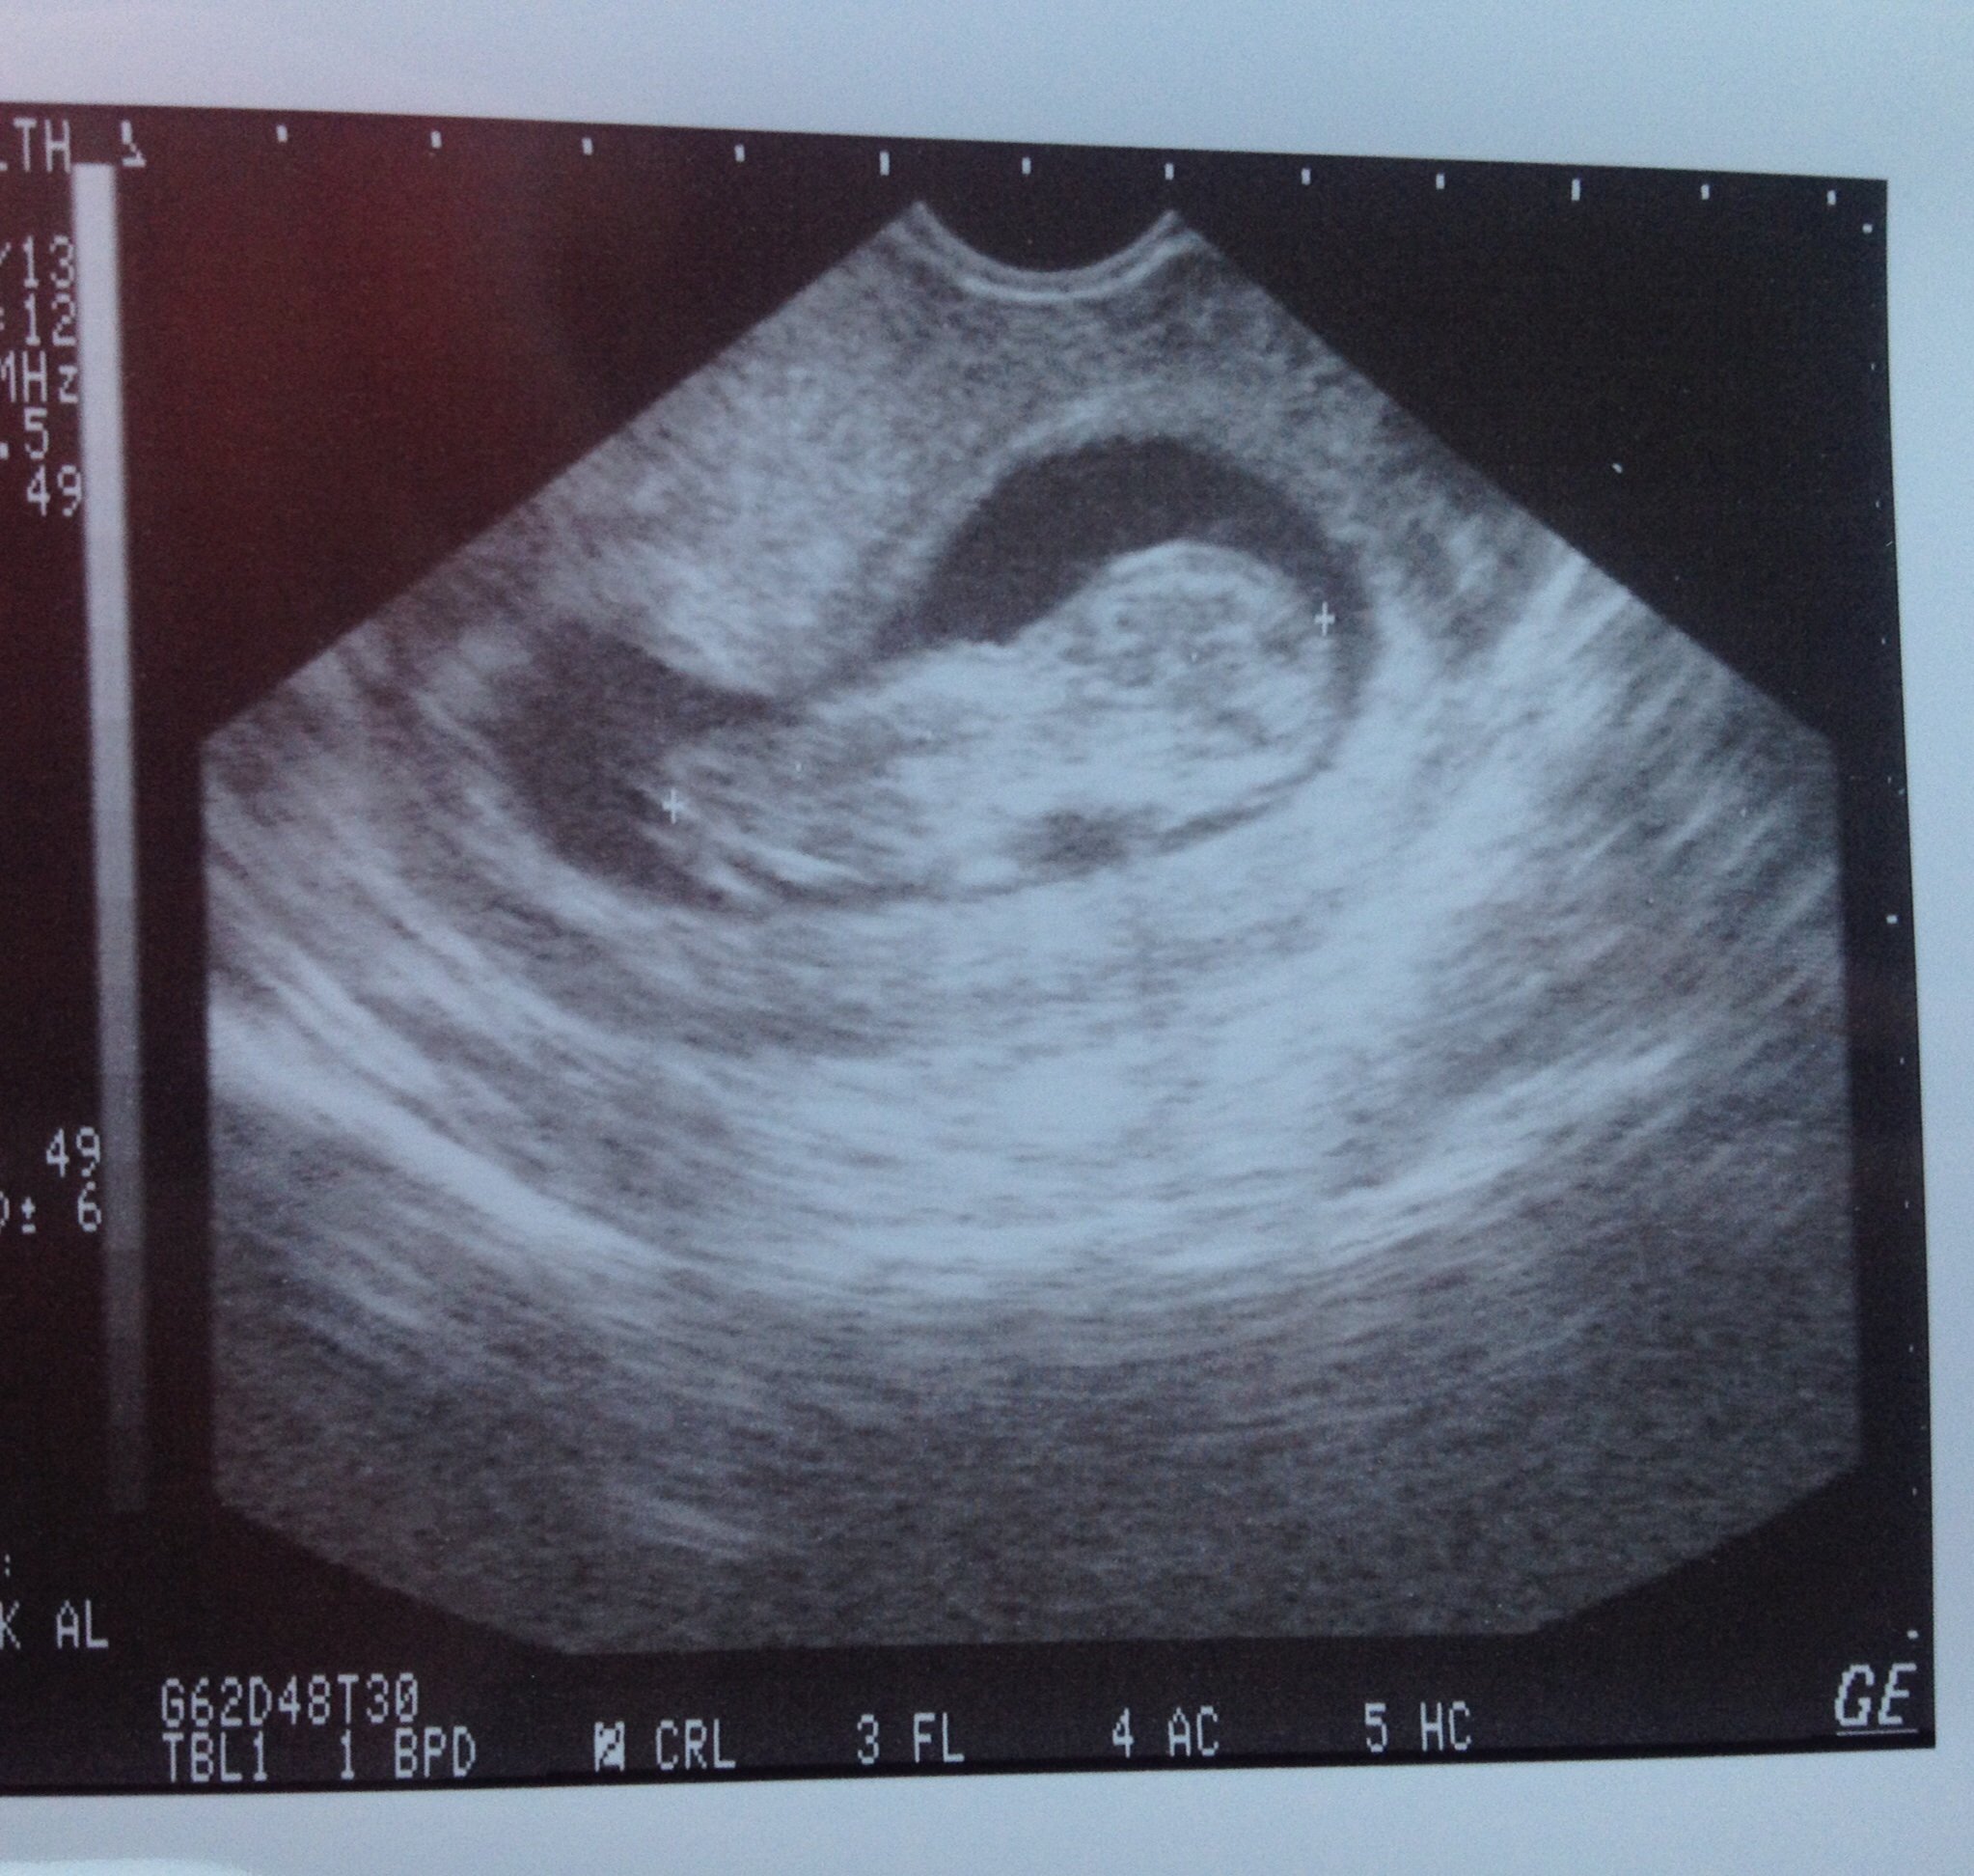

Went in for our second ultra sound today at 11w5d and saw our little one that was moving all over the place! We didn't think about it until after but ask your doctor if you can record it with your phone! The ultra sound pics just don't do it justice!

And here's our little one who has already stolen my heart!